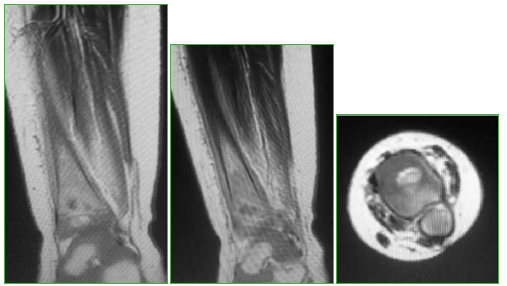

Osteomielitis de tibia secundaria a la vacuna BCG en un paciente pediátrico inmunocompetente. Reporte de un caso

Conclusiones: El compromiso óseo secundario a la vacuna BCG en pacientes previamente sanos es muy raro. Es importante sospecharlo, para diagnosticarlo y administrar el tratamiento adecuado. Se obtuvieron buenos resultados administrando fármacos antituberculosos, sin necesidad de limpieza quirúrgica.